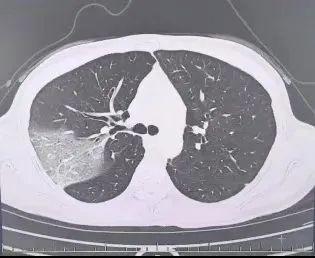

硬扛三天后,程女士在工作会议中不断咳嗽,呼吸困难让她无法集中精力工作。体温高达39.7℃,同事们将她再次送到医院。医生发现她口服速福达抗流感病毒后仍反复发热,并咳出黄色浓痰。检查结果显示,她的好几叶肺都出现了“白肺”现象,指间血氧饱和度只有88%,心肌酶谱、肌钙蛋白和肝功能指标也明显异常。最终,程女士被诊断为重型流感并住院治疗。经过七天的悉心救治,她顺利康复出院。